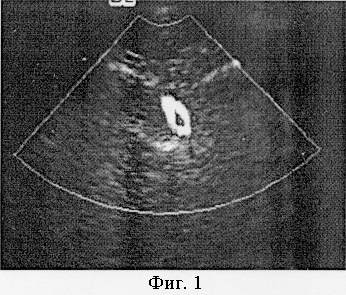

Пример 1. Пациент К. 45 лет, поясничный отдел позвоночника обследовался по поводу остеохондроза с локализацией патологического процесса на уровне L4-L5, при МР-томографии патологических изменений нижнегрудного сегмента позвоночника и дистального сегмента спинного мозга не выявлено. Артерия Адемкевича визуализированная при помощи описанной методики, представлена на фиг.1.